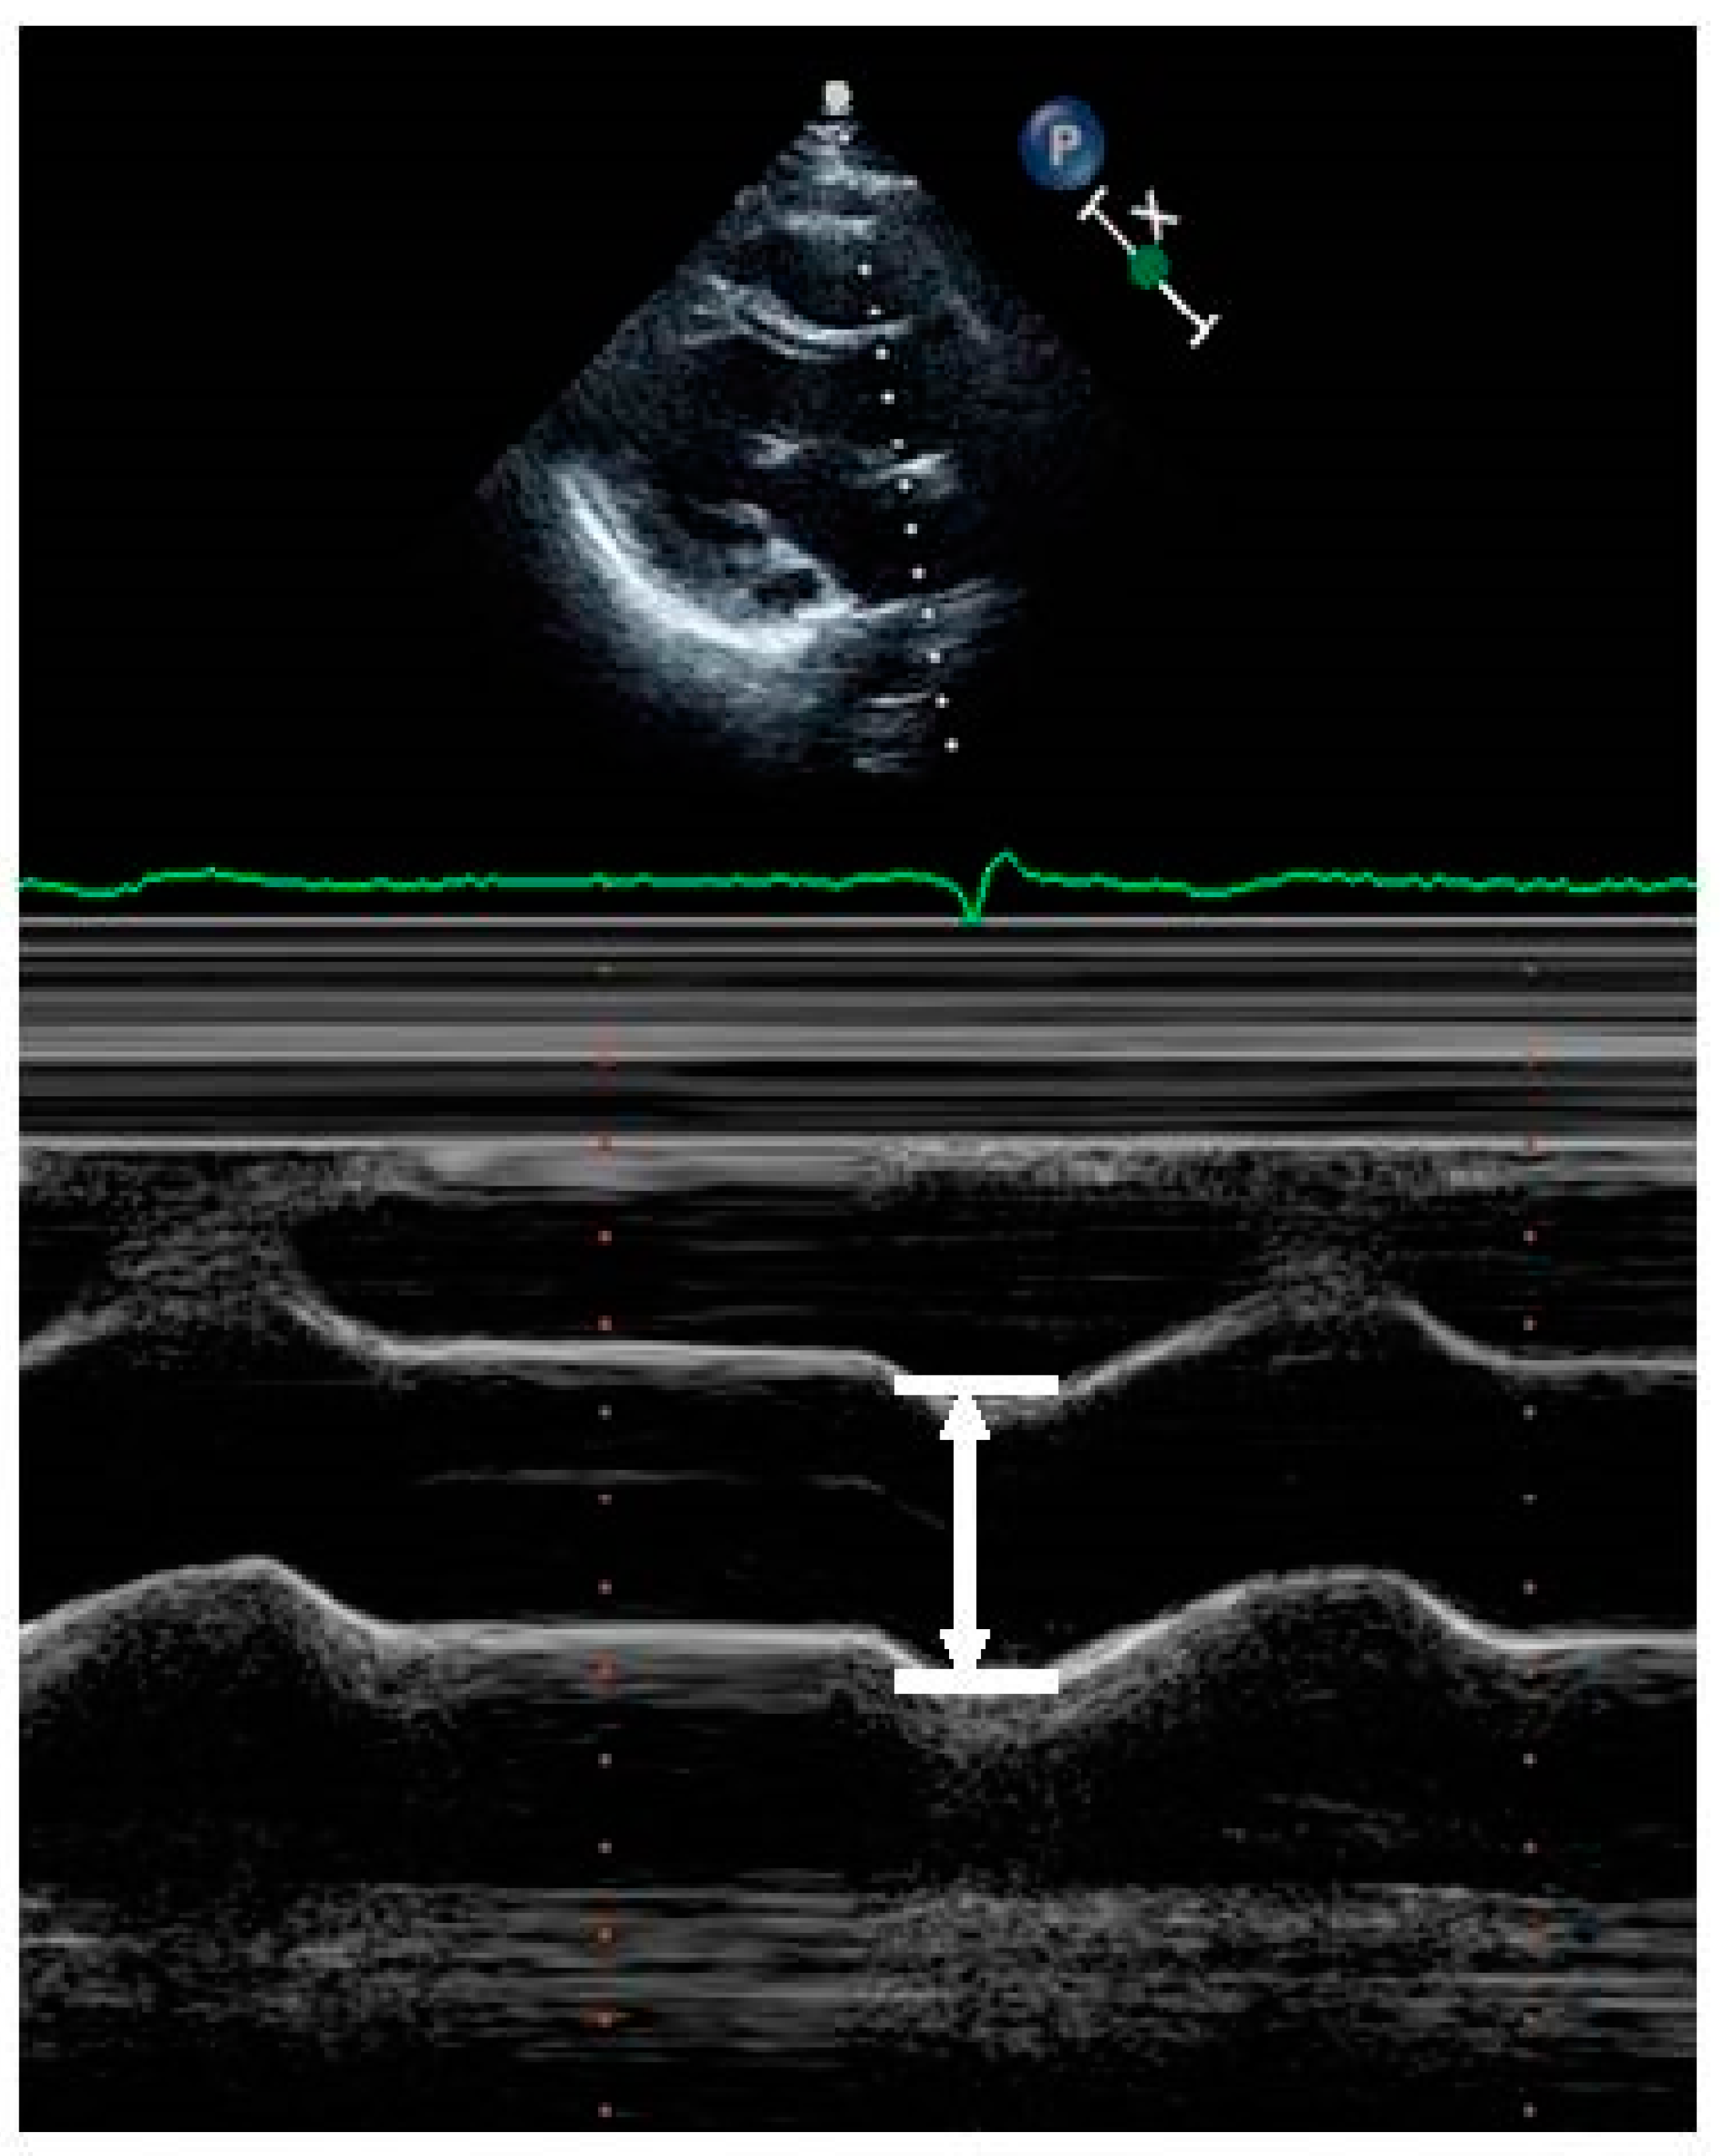

| II | Aortic root diameter (mm) | 34.94 ± 4.18 | 32.66 ± 3.99 | <0.001 |